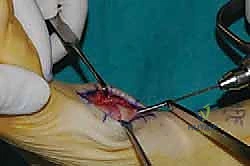

2. الشق الجراحي والوصول للمفاصل

يتم عمل شق جراحي واحد أو شقين (أحدهما في الجزء العلوي الداخلي والآخر في الجزء الخارجي) للوصول إلى مفاصل منتصف القدم دون الإضرار بالأوتار الحيوية والأعصاب والأوعية الدموية. يتم استخدام تقنيات الجراحة الدقيقة (Microsurgery) للحفاظ على الأنسجة المحيطة السليمة.

6. التثبيت الصلب (Rigid Fixation)

لضمان التحام العظام لتصبح عظمة واحدة صلبة، يجب تثبيتها بقوة هائلة حتى لا تتحرك أثناء فترة الشفاء. يتم استخدام مسامير معدنية متطورة (Screws)، أو شرائح معدنية خاصة (Plates)، أو دبابيس طبية متخصصة (Staples) مصنوعة من التيتانيوم الآمن على الجسم.